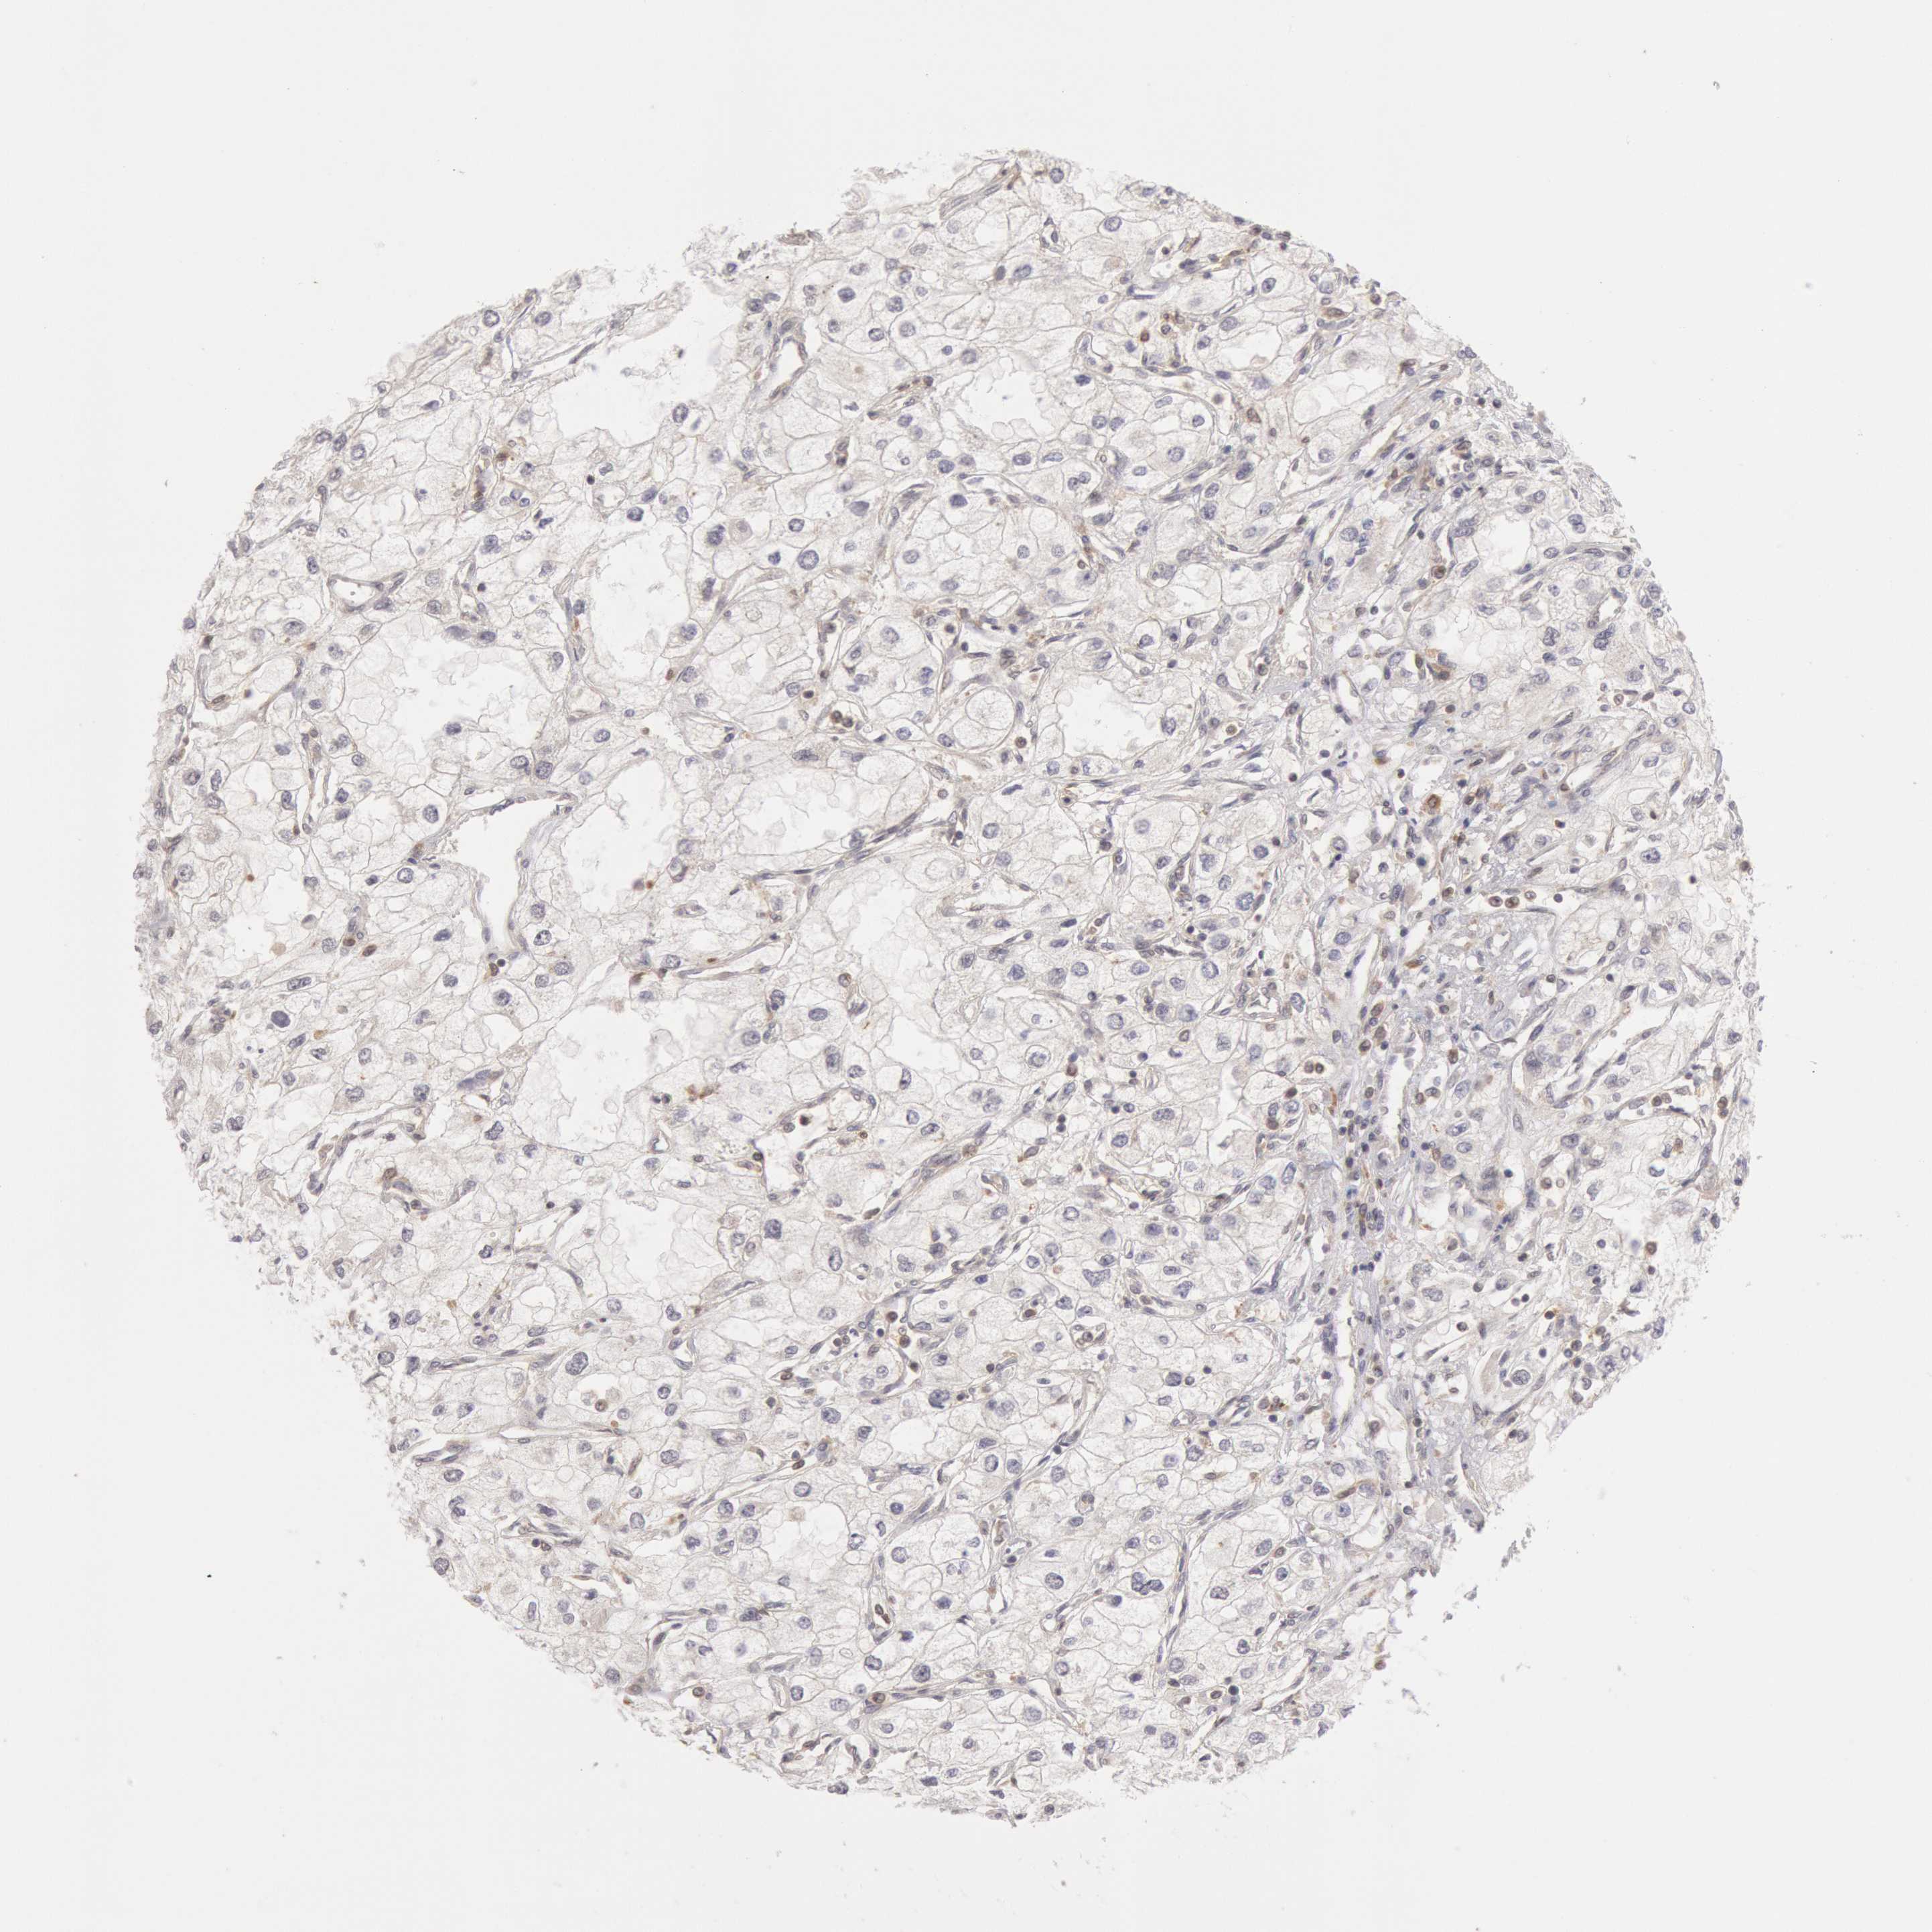

KIDNEY RENAL CLEAR CELL CARCINOMA (VALIDATION) - Interactive survival scatter ploti

The Survival Scatter plot shows the clinical status (i.e. dead or alive) for all individuals in the patient cohort, based on the same data that underlies the corresponding Kaplan-Meier plots. Patients that are alive at last time for follow-up are shown in blue and patients who have died during the study are shown in red.

The x-axis shows the expression levels (FPKM) of the investigated gene in the tumor tissue at the time of diagnosis. The y-axis shows the follow-up time after diagnosis (years). Both axes are complimented with kernel density curves demonstrating the data density over the axes. The top density plot shows the expression levels (FPKM) distribution among dead (red) and alive patients (blue). The right density plot shows the data density of the survived years of dead patients with high and low expression levels respectively, stratified using the cutoff indicated by the vertical dashed line through the Survival Scatter plot. This cutoff is automatically defined based on the FPKM cutoff that minimizes the p-score. The cutoff can be changed by dragging the vertical line or by entering a cutoff value in the square labeled "Current cut-off".

Under the Survival Scatter plot the p-score landscape (black curve; left axis) is shown together with dead median separation (red curve; right axis). Dead median separation is the difference in median mRNA expression between patients who have died with high and low expression, respectively. It is calculated as follows: median FPKM expression of dead patients with high expression - median FPKM expression of dead patients with low expression. This is intended to aid the user in visually exploring custom cutoffs and the associated p-scores and dead median separation.

Individual patient data is displayed and can be filtered by clicking on one or more of the category buttons on the top of the page. Categories describing expression level and patient information include: high, low, alive, dead, female, male and tumor stages. The scale of the x-axis can be toggled between linear and log-scale by clicking on the "x log" button. Mouse-over function shows TCGA ID, patient information and mRNA expression (FPKM) for each patient.

& Survival analysisi

Kaplan-Meier plots summarize results from analysis of correlation between mRNA expression level and patient survival. Patients were divided based on level of expression into one of the two groups "low" (under cut off) or "high" (over cut off). X-axis shows time for survival (years) and y-axis shows the probability of survival, where 1.0 corresponds to 100 percent.

PLA2G6 is not prognostic in Kidney Renal Clear Cell Carcinoma (validation)

Best expression cut offi

Based on the FPKM value of each gene, patients were classified into two groups and association between prognosis (survival) and gene expression (FPKM) was examined. The best expression cut-off refers the FPKM value that yields maximal difference with regard to survival between the two groups at the lowest log-rank P-value. Best expression cut-off was selected based on survival analysis .

When clicking on this number, the vertical dashed line indicating cut-off, the interactive survival plot, and the Kaplan-Meier curve will be adjusted to show results based on the best expression cut-off.

: 8.04

P scorei

Log-rank P value for Kaplan-Meier plot showing results from analysis of correlation between mRNA expression level and patient survival.

N/A

TCGA RNA samplesi

RNA-seq data is reported as average FPKM (number Fragments Per Kilobase of exon per Million reads), generated by the The Cancer Genome Atlas (TCGA) .

Normal distribution across the dataset is visualized with box plots, shown as median and 25th and 75th percentiles. Points are displayed as outliers if they are above or below 1.5 times the interquartile range. FPKM values of the individual samples are presented next to the box plot.

Average pTPM 10.7

Number of samples 100